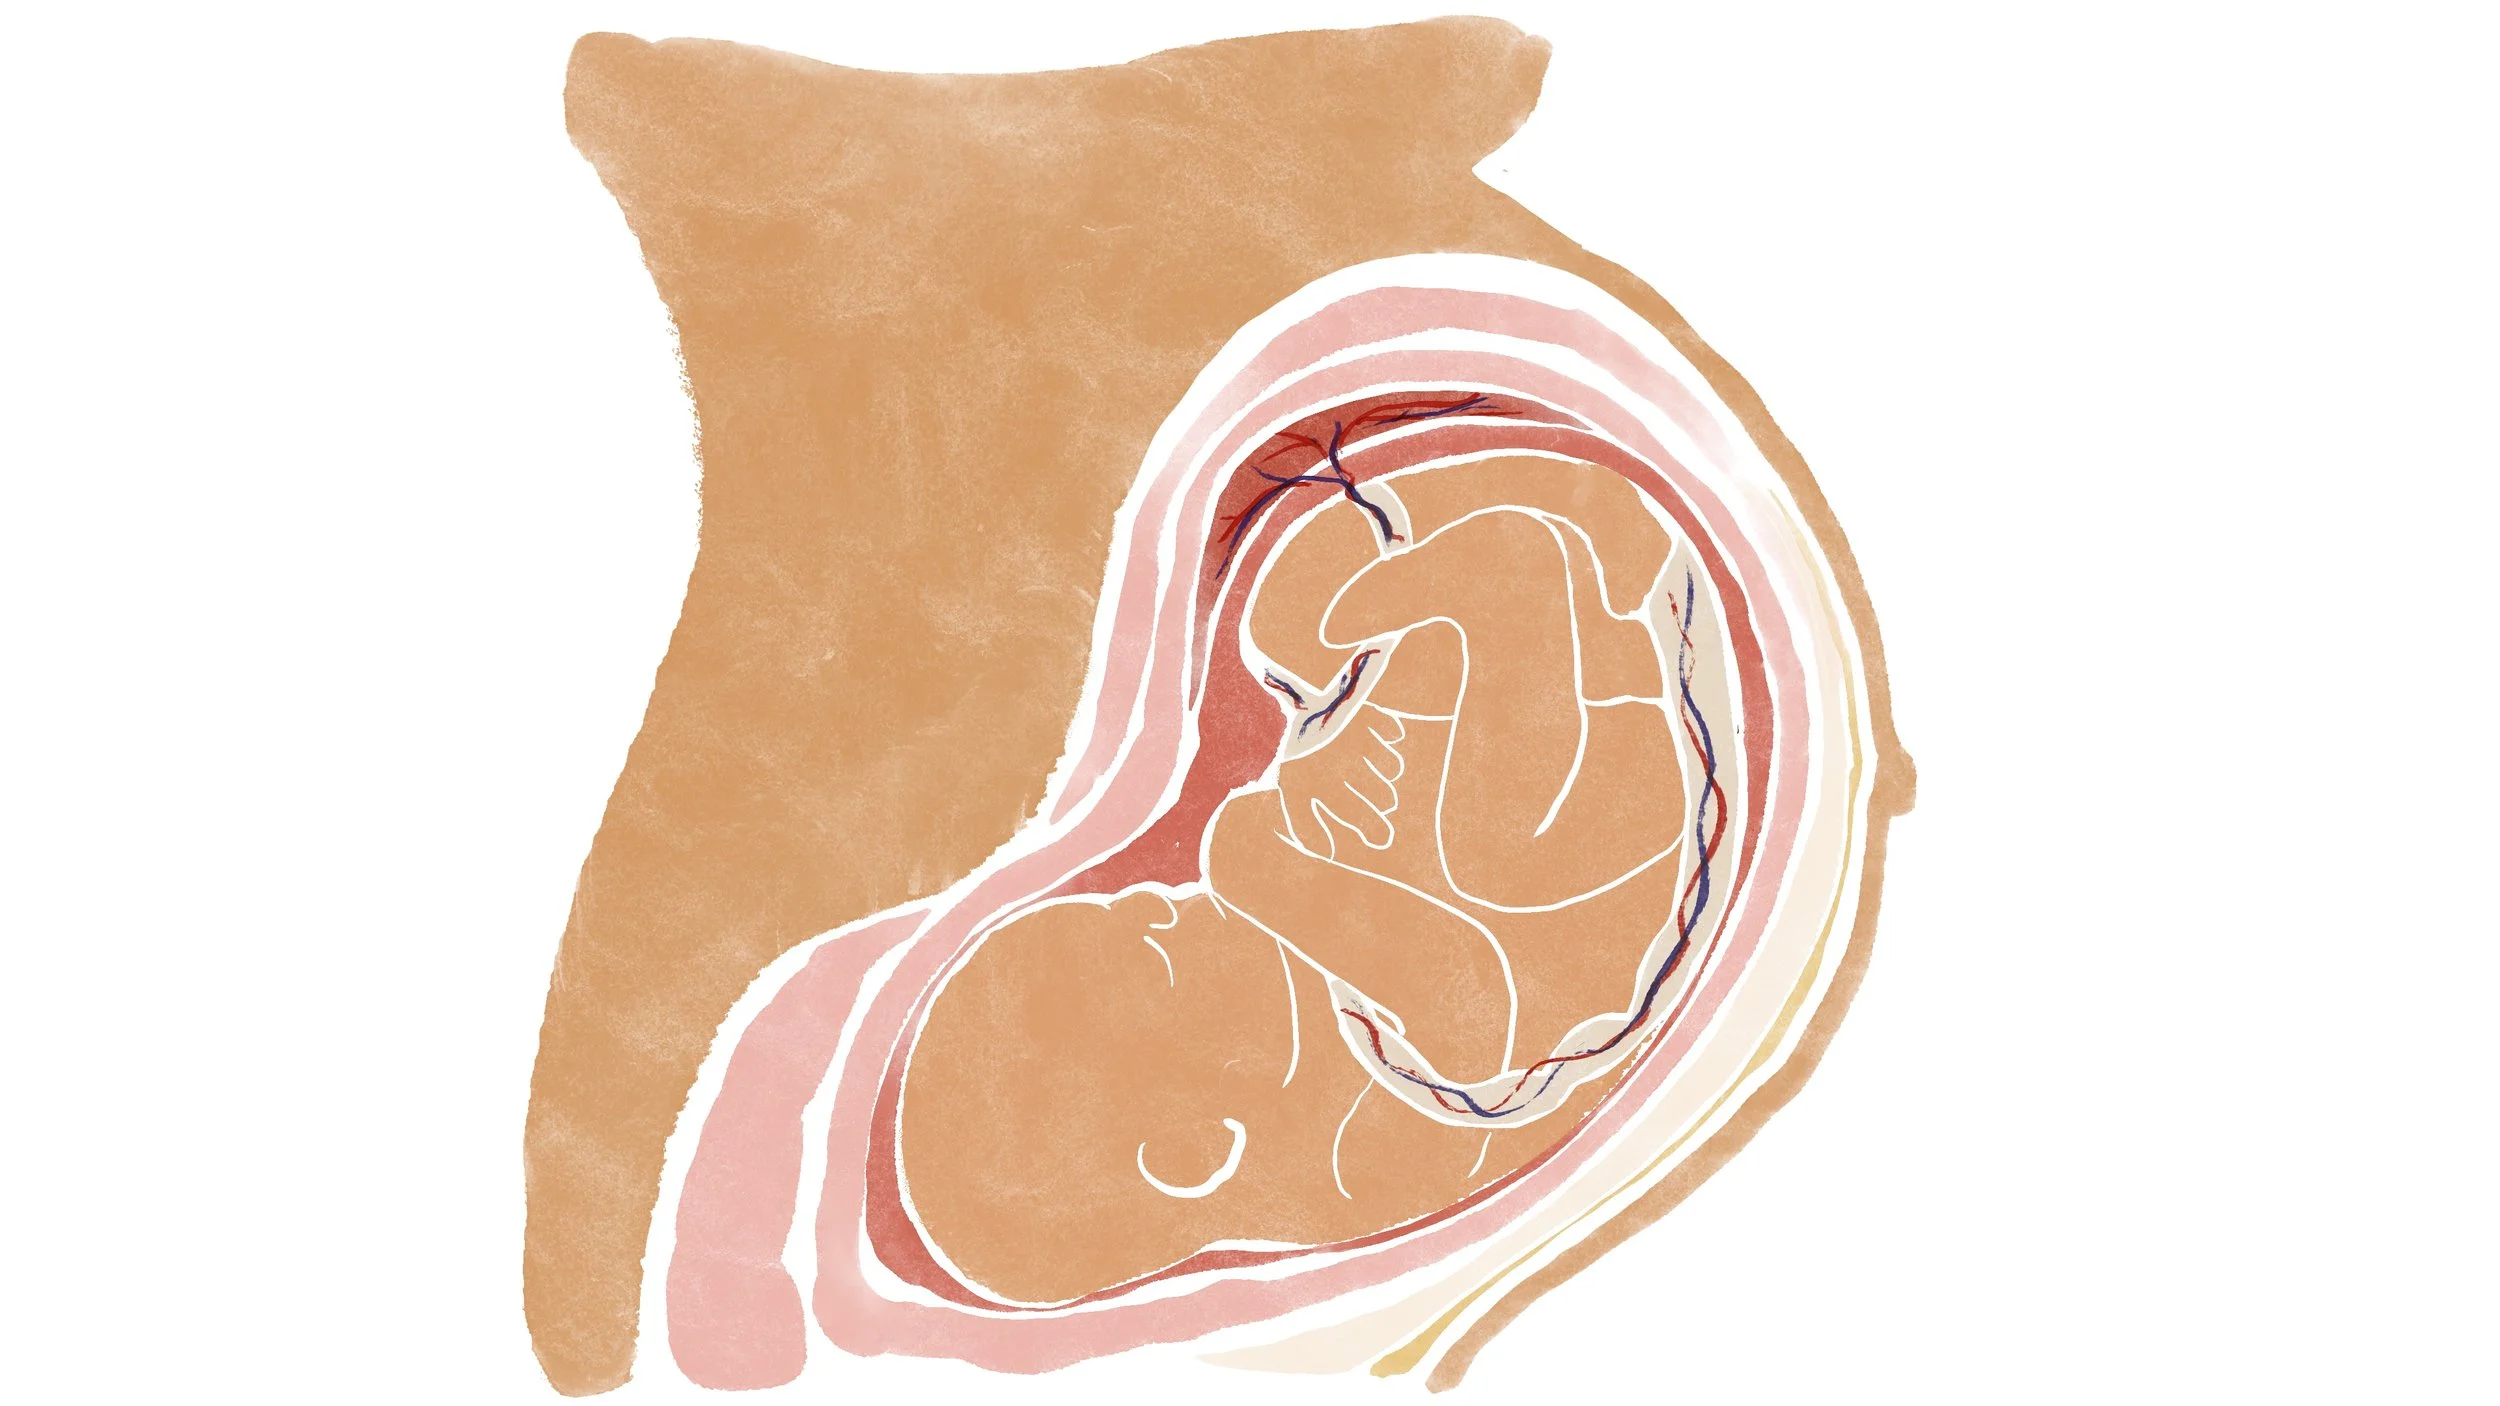

Fetus in womb

Fetus in womb

Fetus in womb